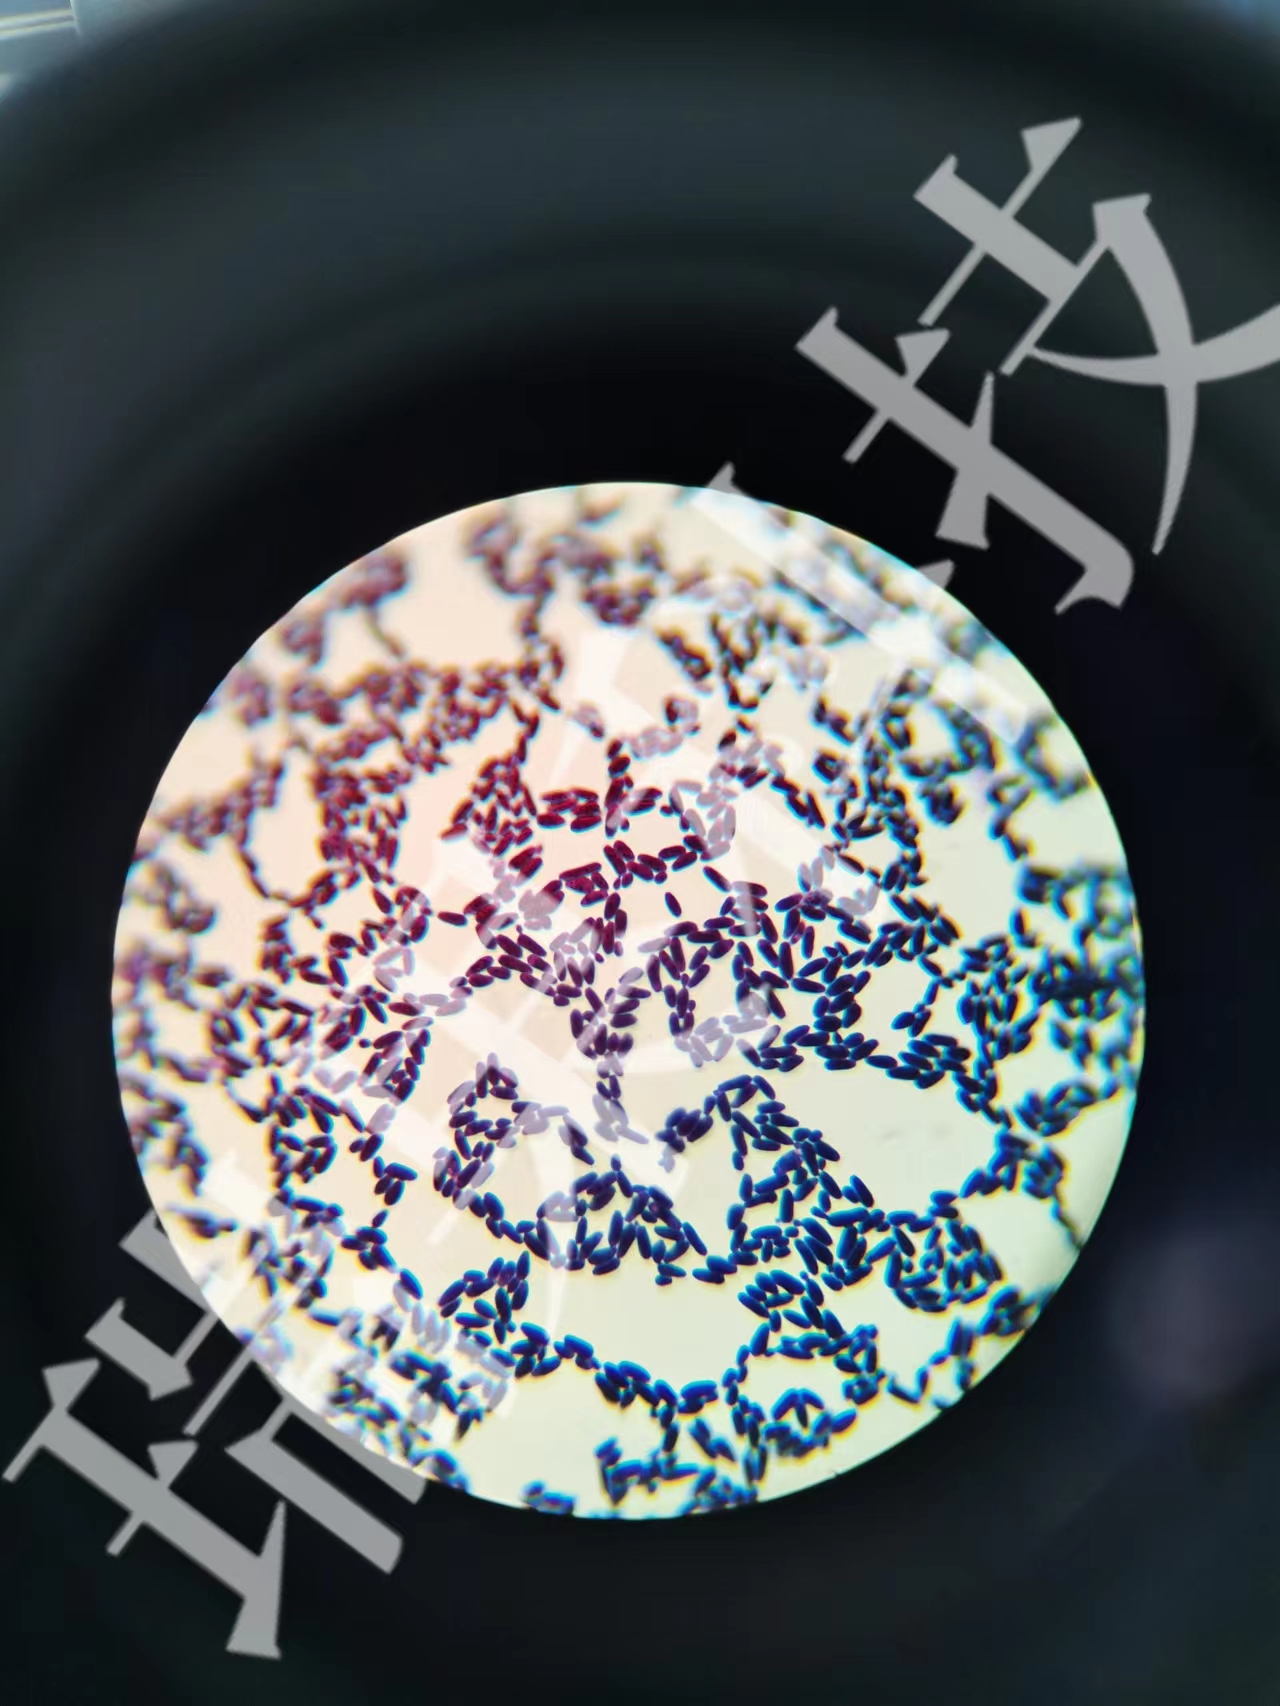

酵母菌革兰氏染色